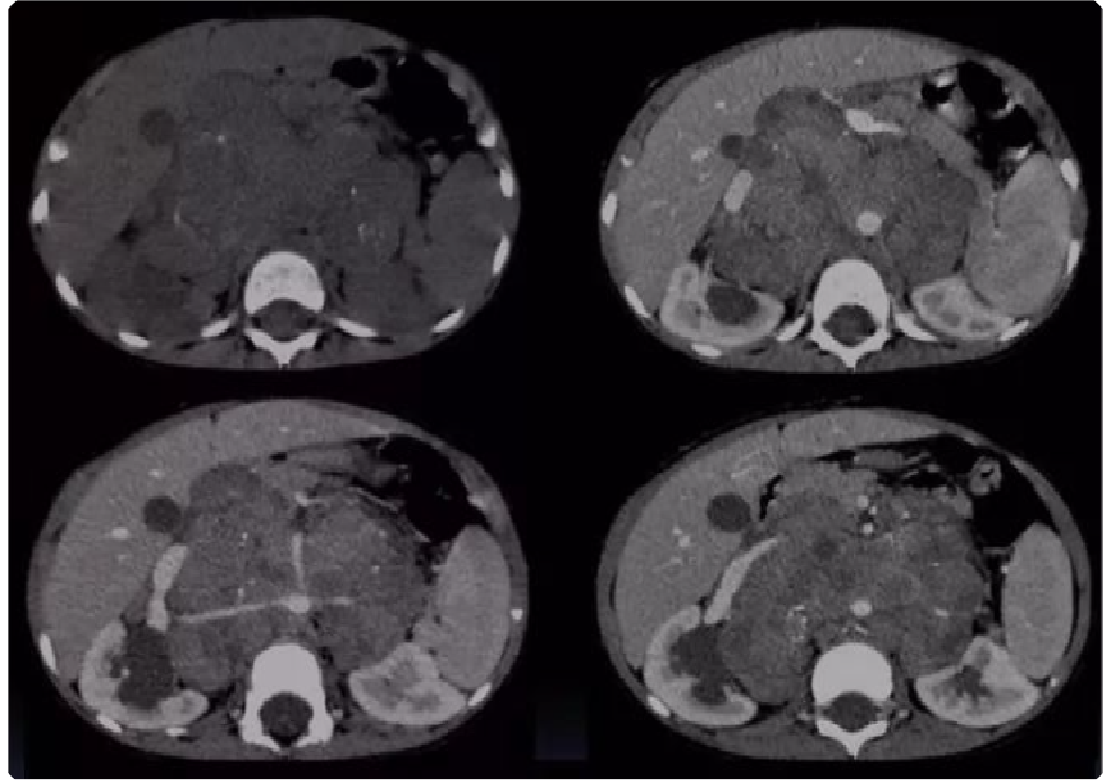

917bfe88330e9a51bacfc381b0a24818.png 病例 6:腹膜后平滑肌肉瘤2例

(① 血管内外;② 血管腔外)① 腹膜后肿块可见侵犯右肾血管、下腔静脉,密度不均匀,有囊变坏死,增强后边缘性延迟环状强化。② 腹膜后肿块与右肾血管,下腔静脉及腹主动脉分界不清,肿块密度不均匀,内可见囊变坏死区及高密度灶(平滑肌肉瘤瘤内如有出血,低密度区内可见高密度出血影,但通常不钙化),增强扫描呈明显不均匀强化,囊变区未见强化。